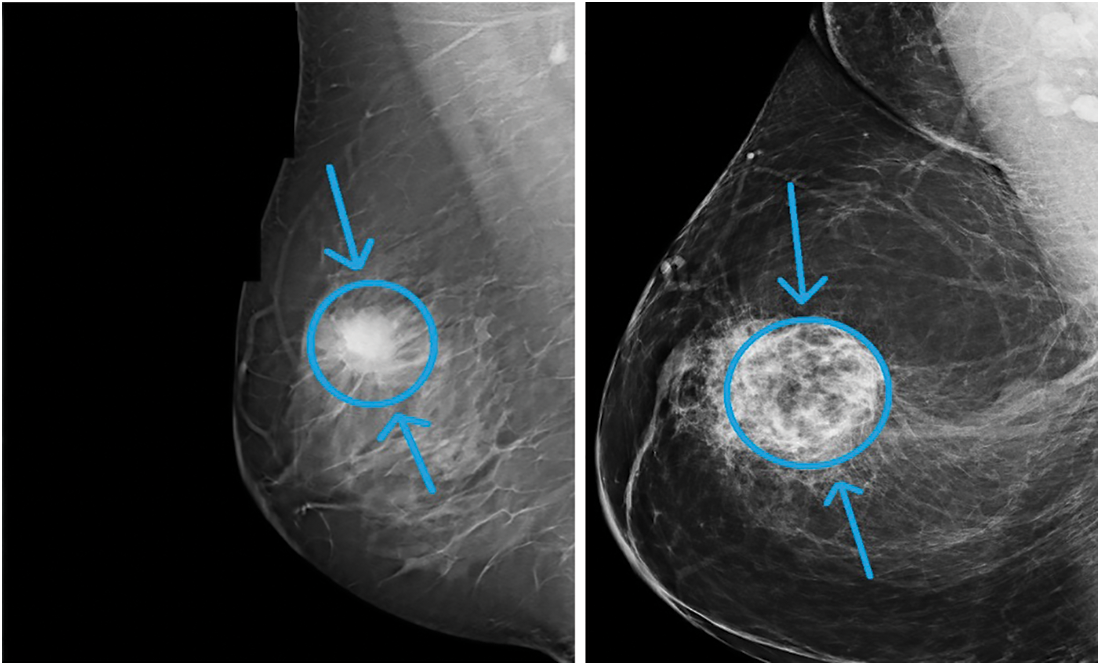

One of the main factors that increases the mortality rate in women worldwide is carcinoma. The number of cancer instances anticipated in 2025 is 19.3 million, the Ministry of Health (WHO) reports. Cancer is a growing issue in Egypt, with carcinoma in particular. As of now, mammography has become one of the key premature breast cancer detection techniques. A more appealing option to mammograms is magnetic resonance testing (MRI). Moreover, MRI is used to verify the presence of cancer by radiologists. MRI is a disadvantage if the person can create an adverse response to the competing drug, or inflammation of the body can grow at the initiation site. As a result, Claustrophobia may be caused. Two major premature indications of cancer, as shown in Fig. 1, are masses and micro calcifications.

Figure 1: Sample breast mammogram